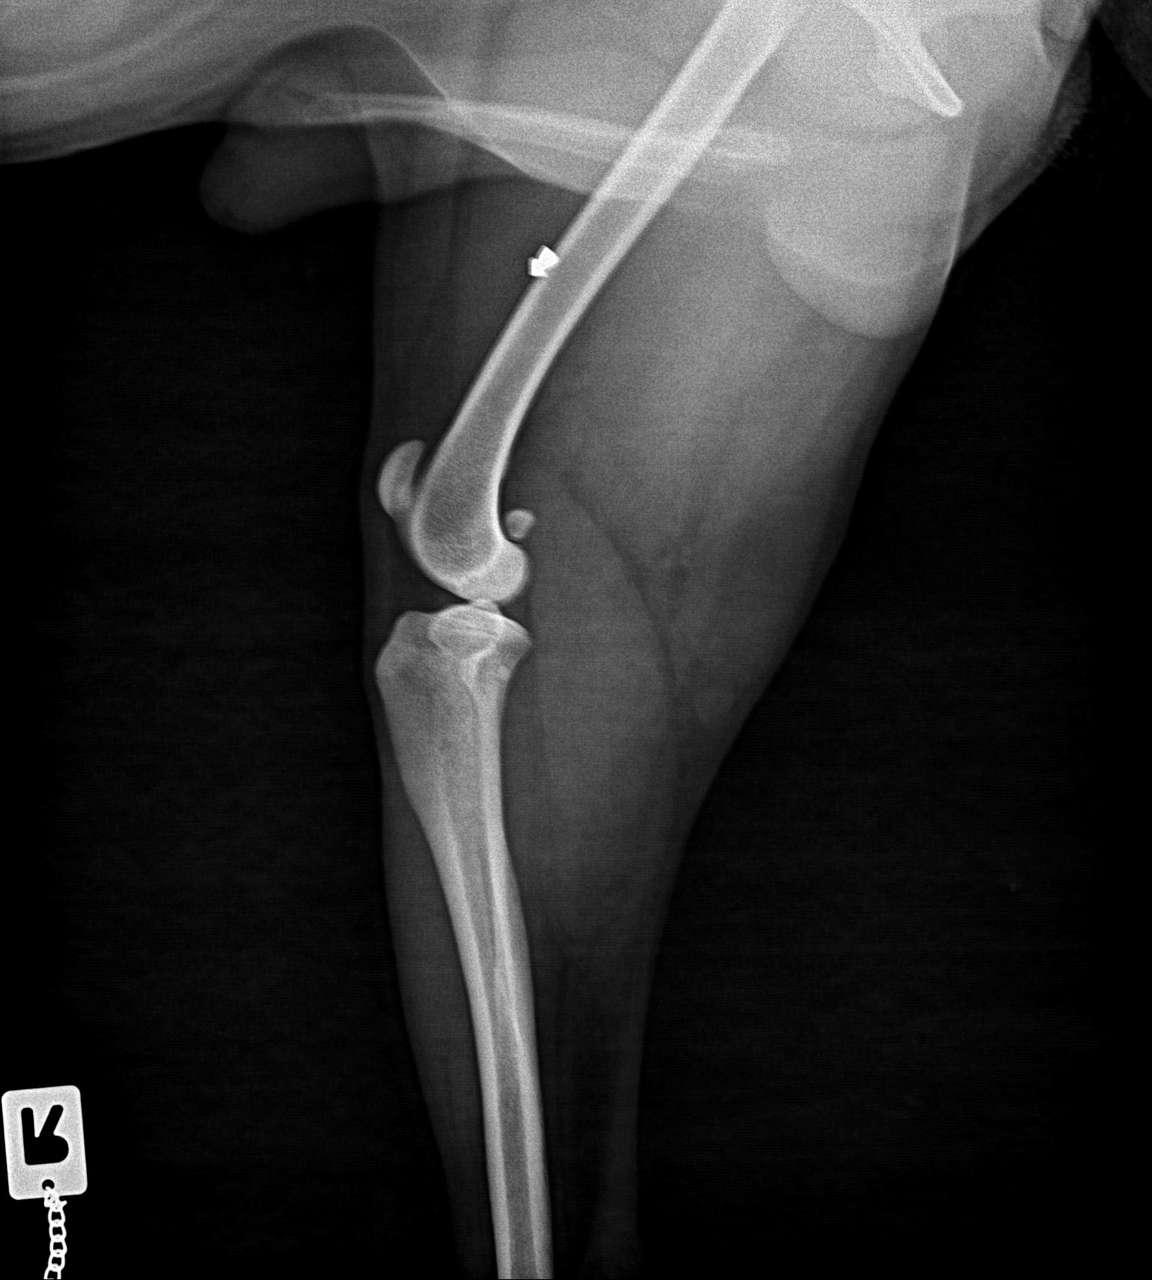

Blossek humpelte, weswegen wir ihn untersuchen ließen. Dabei wurden zwei Geschosse entdeckt.

Wir meldeten ihn bei einem Chirurgen in Berlin an, um die Geschosse entfernen zu lassen. Der Tierarzt fertigte mehrere Röntgenaufnahmen an und entdeckte: 10 Geschosse! In Worten: ZEHN. Und eines davon sogar im Kopf.😭 Wir waren fassungslos.

Zu unserem Erstaunen operierte der Chirurg jedoch nicht. Er untersuchte jedes einzelne Geschoss gründlich und stellte fest, dass Blossek an keiner Stelle Probleme damit hat. Eine Operation hätte also nur kosmetische Gründe. Ein Eingriff wäre eine viel größere Gefahr, erklärte uns der Chirurg.

Es ist einfach toll, wenn ein Tierarzt nur im Interesse des Tieres denkt. Mit Leichtigkeit hätte man uns in dem Fall teure OPs aufschwatzen können.